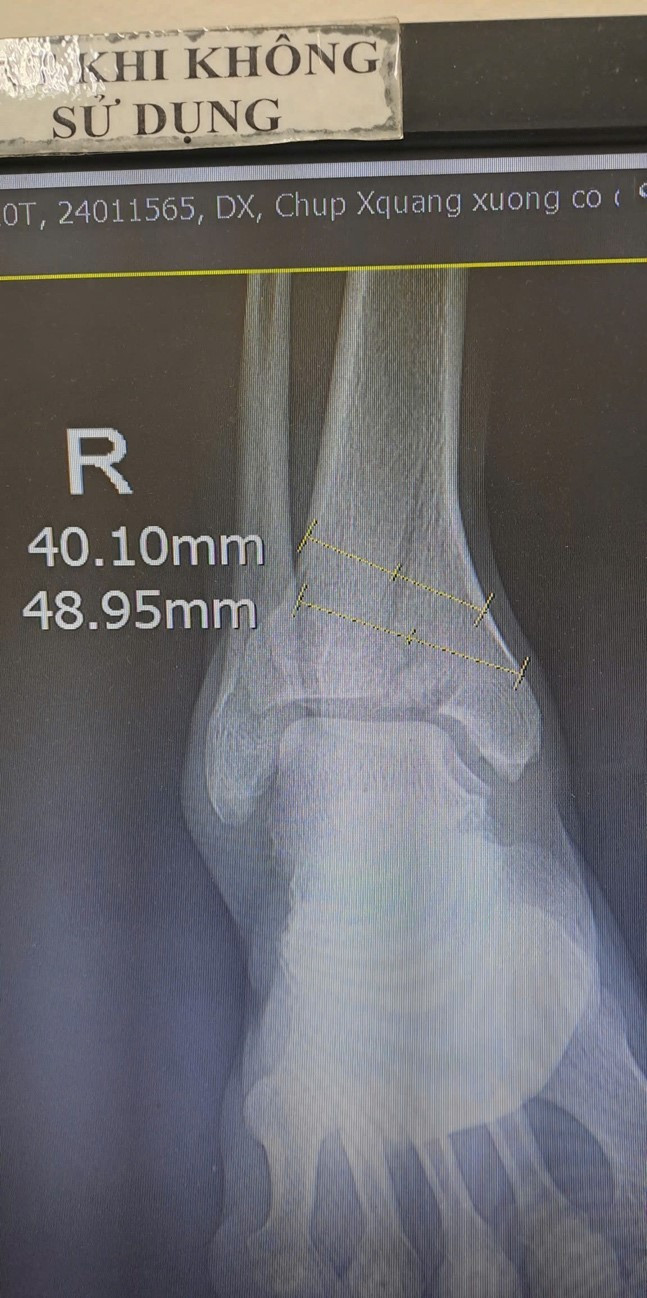

| Hình ảnh xương gãy trên phim chụp - Ảnh BVCC |

Tại đây, bệnh nhân đã nhanh chóng được các bác sĩ thăm khám, qua hình ảnh chụp Xquang, chụp cắt lớp vi tính chân phải kết quả: gãy phức tạp thành nhiều mảnh đầu dưới xương chày một đoạn lên trên khoảng 50mm.

Sau khi hội chẩn chuyên môn và giải thích với người nhà, BS.Nguyễn Đức Hoàn, khoa Ngoại chẩn đoán: Gãy phức tạp đầu dưới xương chày phải phạm khớp – Phân loại Pilon tuyp III (gãy chéo vát, có nhiều mảnh vụn, sập trần xương chày, di lệch mặt khớp). Và lên kế hoạch phẫu thuật cho người bệnh.